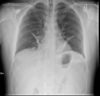

130

Insuficiencia cardiaca

Rx en insuficiencia cardiaca

A: edema alveolar B: líneas B de Kerley C: cardiomegalia D: dilatación de vasos en lóbulos superiores E: derrame pleural